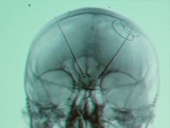

Elektroden im Kopf gegen Depressionen? Klingt martialisch, hilft aber

Manchen depressiven Patienten kann mit den besten Medikamenten oder Psychotherapie nicht geholfen werden. Sie gelten als therapieresistent. Jetzt gibt es einen Hoffnungsschimmer und zwar die sogenannte tiefe Hirnstimulation. Erste Ergebnisse aus klinischen Studien sind vielversprechend. Beim Kongress der Deutschen Gesellschaft für Psychiatrie und Psychotherapie, Psychosomatik und Nervenheilkunde (DGPPN) in Berlin (26.-29.11.2014) wurden die Erkenntnisse vorgestellt.

Die Bezeichnung tiefe Hirnstimulation sagt eigentlich schon alle. Tief im Hirn wird stimuliert und dafür ist ein Eingriff nötig, der durchaus martialisch klingt. Das gibt auch Thomas Schläpfer zu. Er ist Leiter des DGPPN-Referats "Experimentelle Stimulationsverfahren in der Psychiatrie"

Tief im Gehirn geben die Elektroden dann laufend leichte Stromstöße ab und beeinflussen so das Belohnungssystem.

Erste Studienergebnisse untermauern diese These. 75 Prozent der Patienten reagierten merkbar auf die Therapie.

Noch werden weitere Studien geplant. In vier Jahren könnte das Verfahren zugelassen sein und angewendet werden.